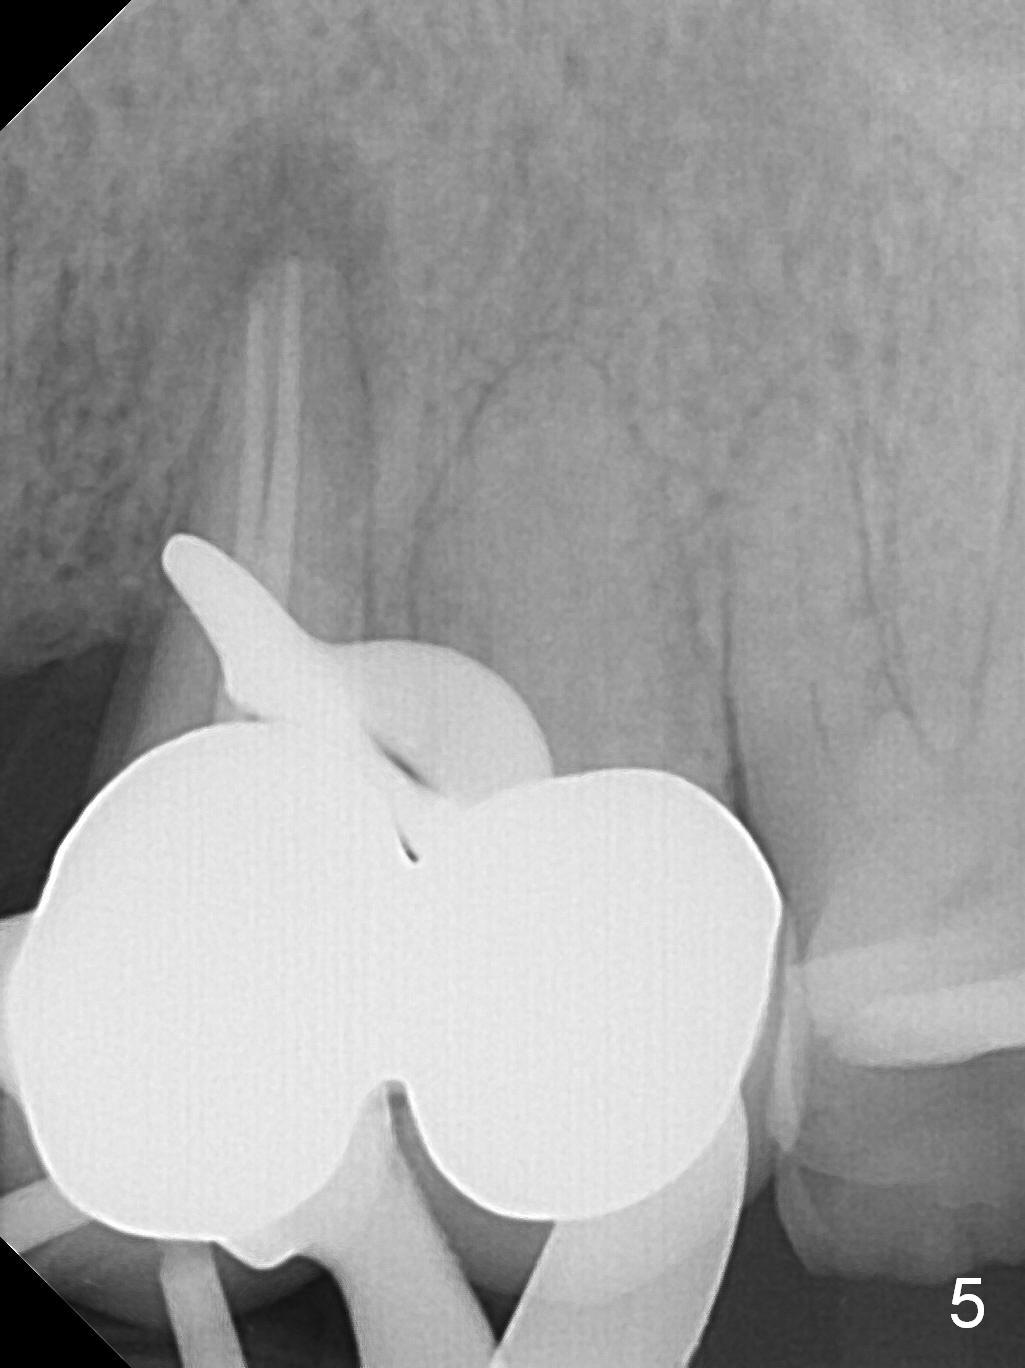

A 43-year-old woman has a persistent, asymptomatic fistula buccal to the tooth #12 (Fig.1,2). Prior to treatment, a #30 gutta percha is inserted into the fistula to confirm diagnosis (Fig.3). Hand files #15 and 20 are inserted to the buccal and lingual canals at 18 mm, respectively (Fig.4). Master cones (30/.04) are inserted buccally and lingually for 18 and 17 mm, respectively (Fig.5). There is minimal paste leakage after finishing RCT (Fig.6). Out of curiosity, the fistula is immediately curetted with removal of 2 small pieces of apparently leaked paste with minimal discomfort (total anesthetic: Xylocaine 34 mg, Epi 17 mcg). The fistula is expected to heal in 2 weeks.